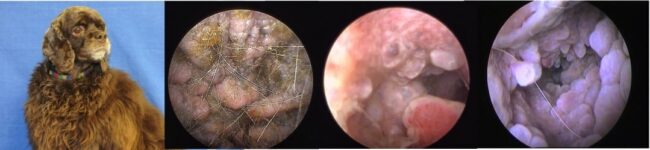

Otites du Cocker Américain : une Maladie Génétique

L’hyperplasie primaire des glandes cérumineuse est une des plaies du cocker américain, générant des otites graves le plus souvent incurables. Elles demeurent une indication d’ablation du méat sur des animaux assez jeunes (TECALBO). Une étude finlandaise récente montre qu’il existe sur le chromosome 31 probablement un gène candidat de cette hyperplasie primaire. Cette même étude…